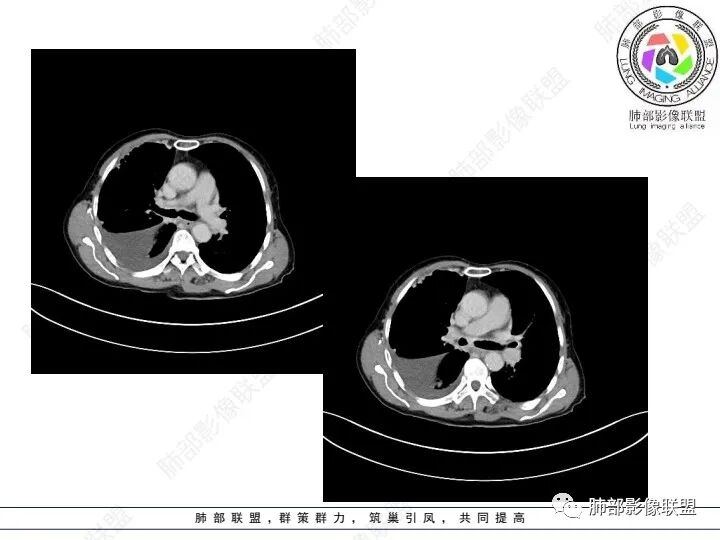

老年女性,肺气肿背景。腹痛、便血入院。右肺下叶脊柱旁软组织肿块,强化不均匀,中心有坏死,纵隔及双侧肺门多发肿大淋巴结、有融合,右下支气管周围为主,包绕支气管生长,且管壁增厚伴环形钙化、狭窄,增强后有环形强化。右侧胸膜见结节灶,增强后明显强化;右侧胸腔积液。考虑:右下肺恶性肿瘤伴纵隔、肺门多发肿大淋巴结,胸膜转移,低分化腺癌?Ca125明显升高,老年女性 是否有妇科恶性肿瘤?黏液腺癌 肺内、纵隔转移?

右肺下叶类圆形软组织密度影,纵隔及肺门多发肿大淋巴结、有融合,右下肺支气管壁增厚伴环形钙化、狭窄,右侧胸膜见结节灶,增强后均匀明显强化;右侧胸腔积液。考虑:右肺下叶肿瘤伴纵隔肺门、胸膜转移,考虑腺癌可能。

老年女性,右肺下叶后基底段实性肿块,边缘强化明显,坏死,形态湖泊状,坏死轮廓不清,右肺门下方淋巴结肿大融合,包绕右肺下叶支气管血管束开口,右肺脏层及叶间胸膜多发转移强化结节,右侧胸腔积液,肺气肿背景,支持恶性,肺腺Ca,右肺下叶肿块经皮肺穿刺活检,另消化道岀血,Ca125值明里高,与肠Ca,补充腹部CT平扫及增强和肠镜检查,肠Ca右肺转移待排。

女,69,腹痛、便血4小时。CA125增高。胸部CT:肺气肿背景。右下叶不规则肿块影,处于外周气肿带与正常肺交界区,强化不均匀,中心有坏死;纵隔及肺门多发肿大淋巴结、融合,包绕支气管,部分钙化、环形强化;右下支气管周围管壁增厚伴环形钙化、狭窄。右侧胸膜多发结节灶,增强后明显强化,右侧胸腔积液。考虑恶性,右下肺腺Ca多发转移?转移瘤?鉴别TB、IgG4等。

3、胸部增强CT示右肺下叶脊柱旁不规则软组织肿块,侵及壁层胸膜外,密度不均匀,不均匀强化,中心低密区可疑坏死,右侧胸腔积液、胸膜结节影或结节样增厚,增强扫描可见强化,右侧肺门及纵隔内可见淋巴结肿大、融合,右侧中尖段支气管及右肺下叶支气管受侵,管腔狭窄。

4、综上,老年男性,CA125升高,右肺下叶肿块侵犯胸壁,伴纵隔、右肺门及纵隔淋巴结肿大,右侧胸腔积液、胸膜增厚伴结节影,强化明显,应该为一较典型的肺癌伴肺胸膜腔及肺门纵隔淋巴结转移,尤其是肺腺癌。